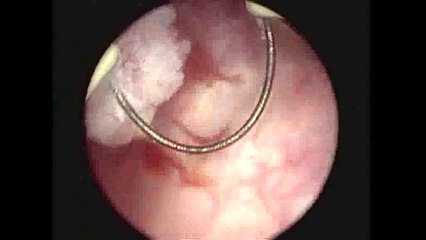

Bladder Tumour Operated By DR. IMTIAZ ALI (Urolgist)

Removing of a Bladder Tumour Operated By DR. IMTIAZ ALI (Dr.